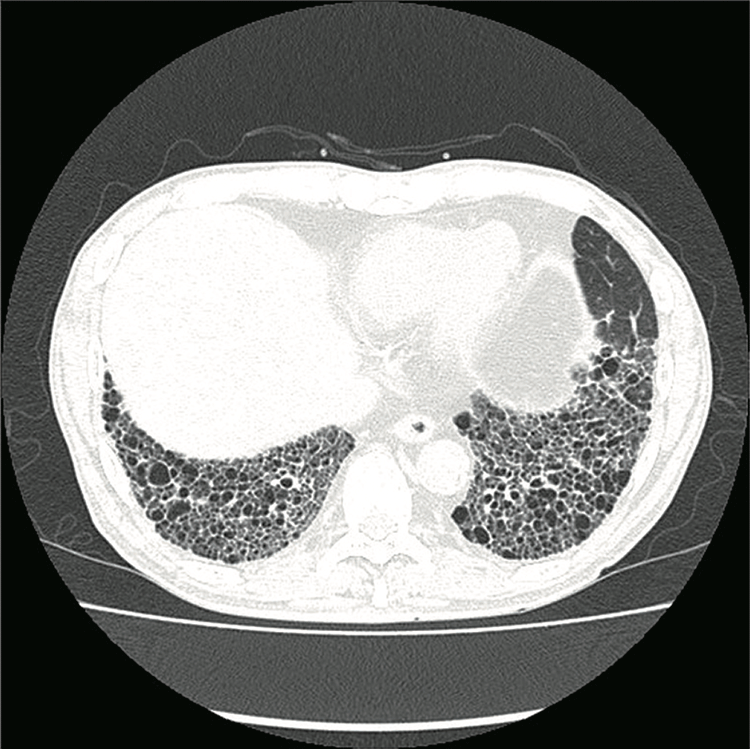

一方、詳しく調べても原因がわからない間質性肺炎もあり、これは「特発性間質性肺炎」と呼ばれます。この特発性間質性肺炎の中でも最も頻度が高く治療が難しいのが「特発性肺線維症」ですが、肺が硬くなり、胸部CTではあたかもハチの巣のように見えるため、「蜂巣肺(はちそうはい)」と呼ばれます(図3)。